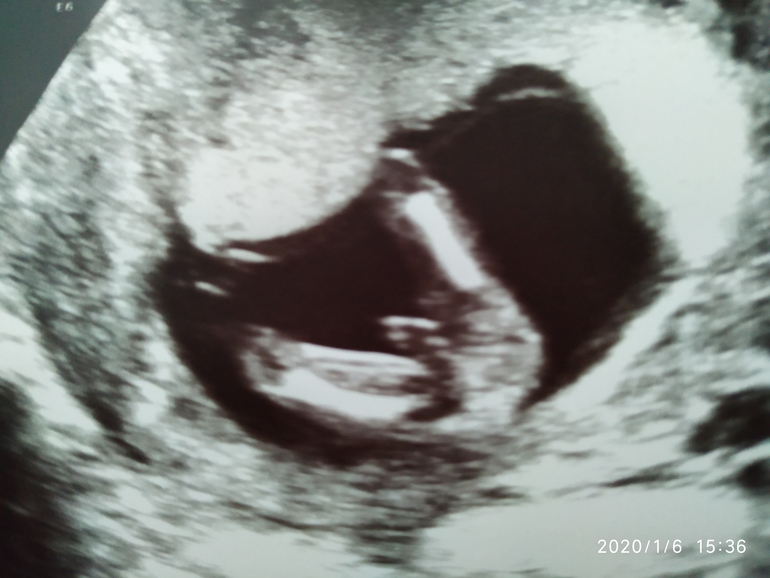

Так не большое, это нога согнута и стопа между ног :) а пол не очень пока видно. Недели через 2 точно уже будет видно.

Если честно, мне видится девочка. 2 полосочки это губы и поменьше клитор. А на фото в профиль бугорок не видно,клитор длинный в этом сроке и можно спутать с пенисом.

Половой бугорок Мальчик девочка?